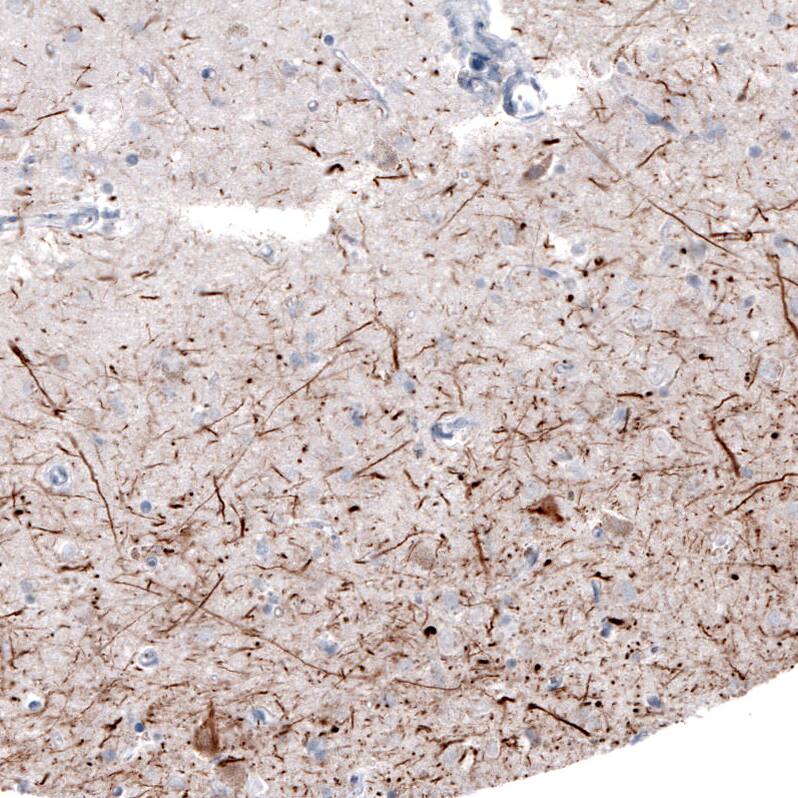

NF-H Antibody (CL2671) - Azide and BSA Free Immunohistochemistry-Paraffin: NF-H Antibody [NBP3-43795]

Immunohistochemistry-Paraffin: NF-H Antibody [NBP3-43795]

Staining of human cerebellum shows moderate immunoreactivity in Purkinje cells and neural fibers.